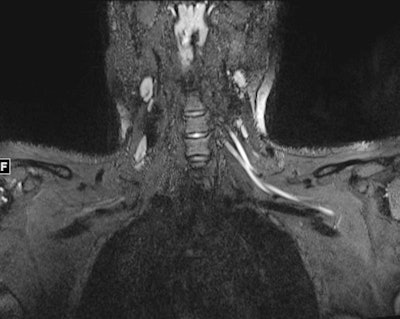

Ultrahigh-resolution ultrasound and MR neurography (which visualizes the peripheral nerves) can localize the problem and assess the severity of nerve damage and whether that damage has affected the muscles, according to the team.

"Peripheral nerve imaging aids diagnosis and may guide management in COVID-19 patients with neuromuscular symptoms arising from the infectious disease, hospitalization course, or secondary to a complication in treatment," the group concluded.